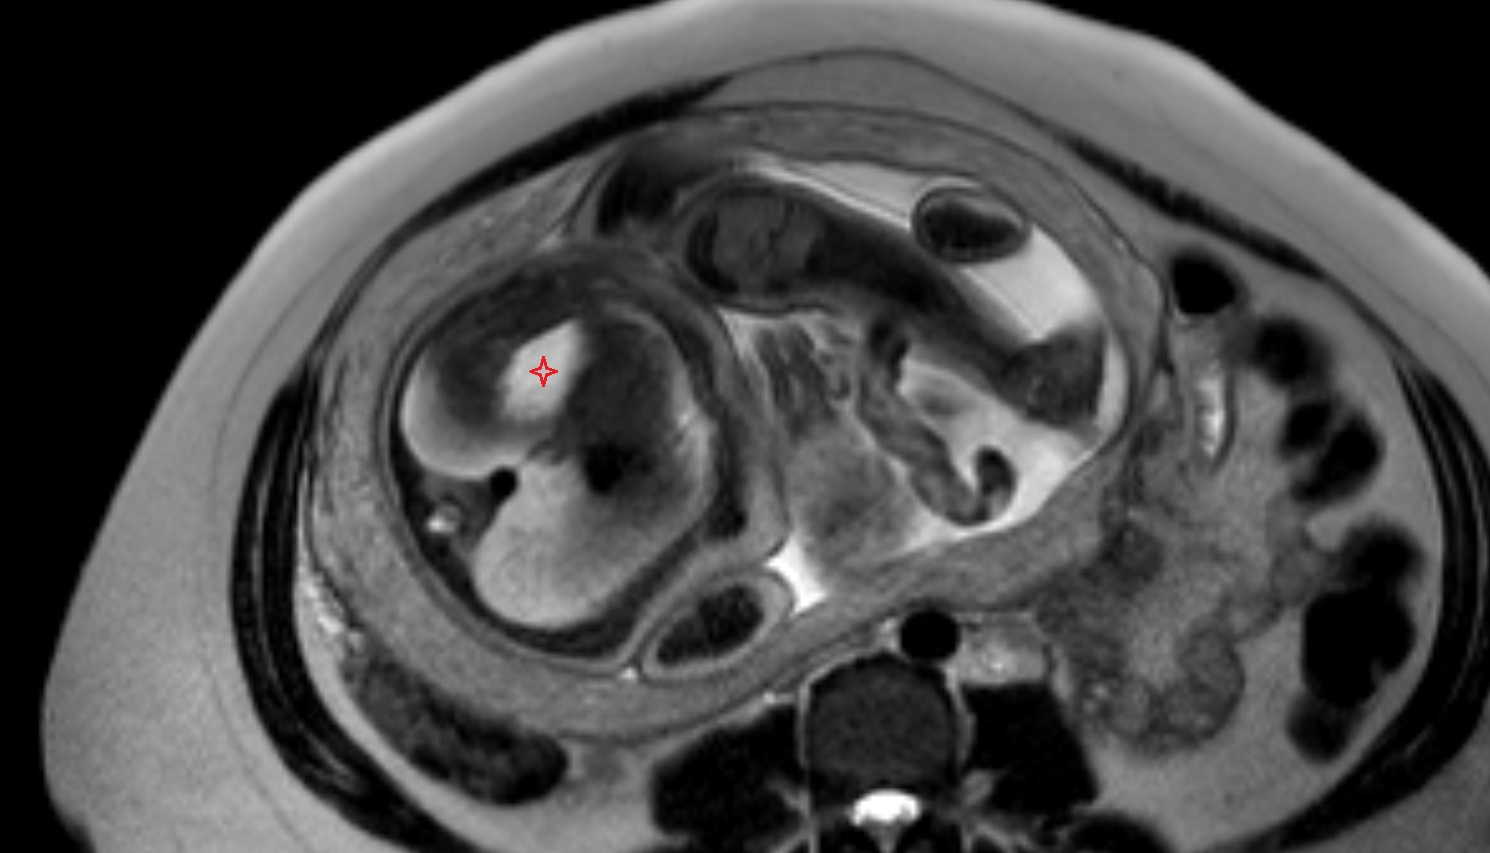

- Placenta

- Uterus (pregnancy)

- Amniotic fluid

- Umbilical cord

- Fetal brain

- Fetal caudate nucleus

- Fetal thalamus

- Fetal cerebellum

- Fetal lateral ventricle